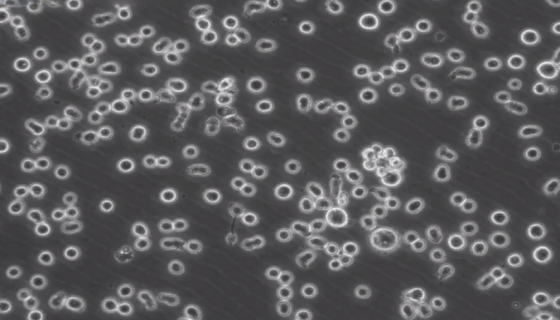

小鼠T淋巴细胞的培养步骤与应用!

小鼠T淋巴细胞是骨髓来源的淋巴干细胞在胸腺内分化而成的。胸腺...